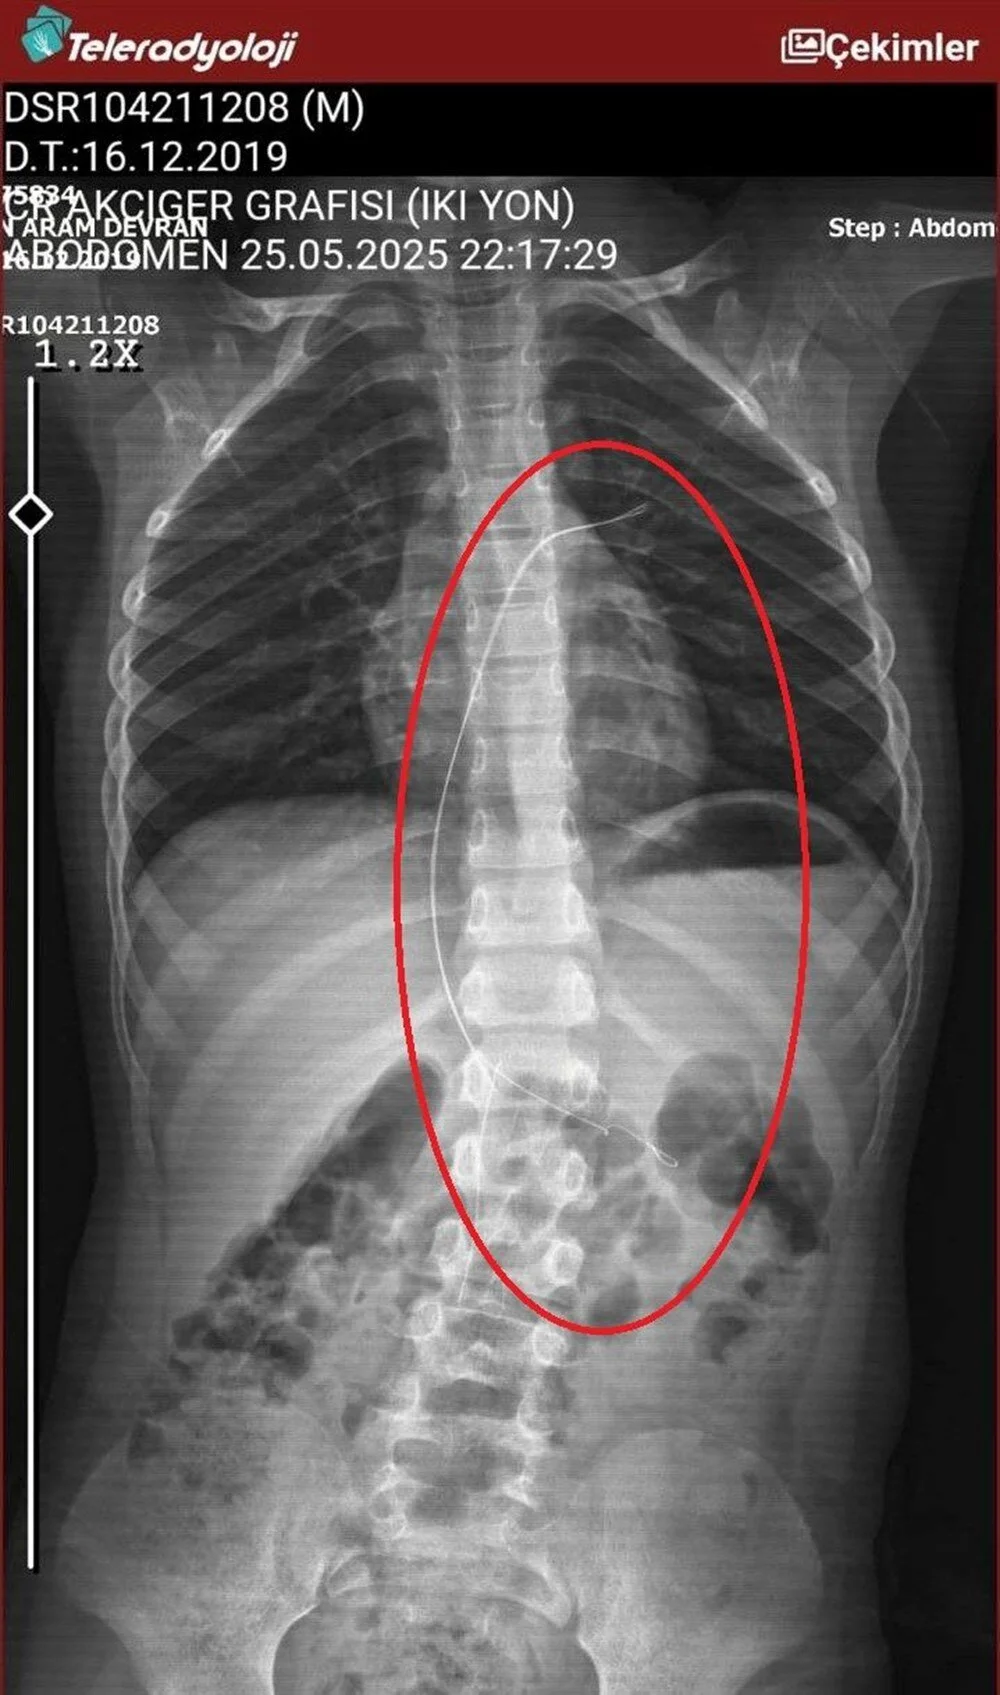

Burada çekilen röntgen ve MR'da Aram'ın vücudunda kateter unutulduğu görüldü.

Diyarbakır'daki Gazi Yaşargil Eğitim ve Araştırma Hastanesi Kadın Doğum ve Çocuk Ek Binası'na sevk edilen Aram, 5,5 saat süren riskli bir ameliyata alınarak 18 santimetre uzunluğundaki kateter çıkarıldı.

Gece saatlerinde çocuklarını hastaneye götürdüklerini anlatan anne, "Doktor röntgeni gösterdi. Tel kalmıştı. Çok kötü bir şekilde. Acil doktoru film çektikten sonra bize bir tel parçasını gösterdi. Bizi bekletmeden Diyarbakır’a sevkimizi verdiler." dedi.